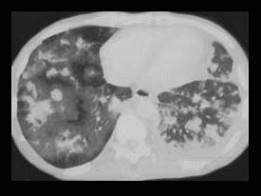

问题 男,27岁,干咳,呼吸困难半月余,有艾滋病病史半年余,请结合CT检查,选出最可能的诊断 ( )

选项 A、矽肺 B、Kaposi肉瘤 C、弥漫型肺癌 D、间质性肺炎 E、粟粒型肺结核

答案 B